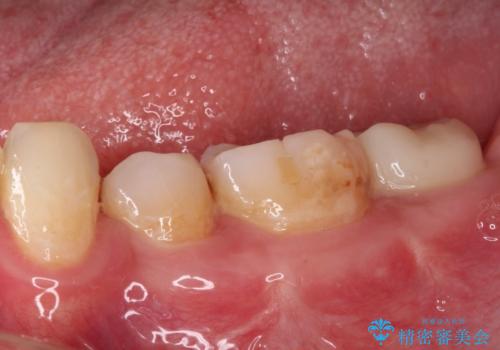

- 左下欠損部のインプラント治療と、右下の歯の痛みを気にして来院された患者様です。

左下の欠損部は、世界中で高い信頼を得ているストローマンインプラントを用いて治療を行うこととしました。

ただし、長期間欠損を放置していたことで、咬み合う上の奥歯が動いてしまっていたので、まずは上顎奥歯の部分矯正を行い、より理想的な咬み合わせを目指すこととしました。

右下の歯は、レントゲン上歯髄組織まで虫歯が及んでいるように見えましたが、痛みの症状は強くなかったため、歯髄組織の一部を断ち歯根部分の組織を保存する生活歯髄療法を第一選択に処置を進めて行くこととしました。

まず生活歯髄療法を行い、その後部分矯正やインプラント処置を行いましたが、最初の処置から1年以上経っても右下奥の処置歯の神経組織に異常は認められませんでした。